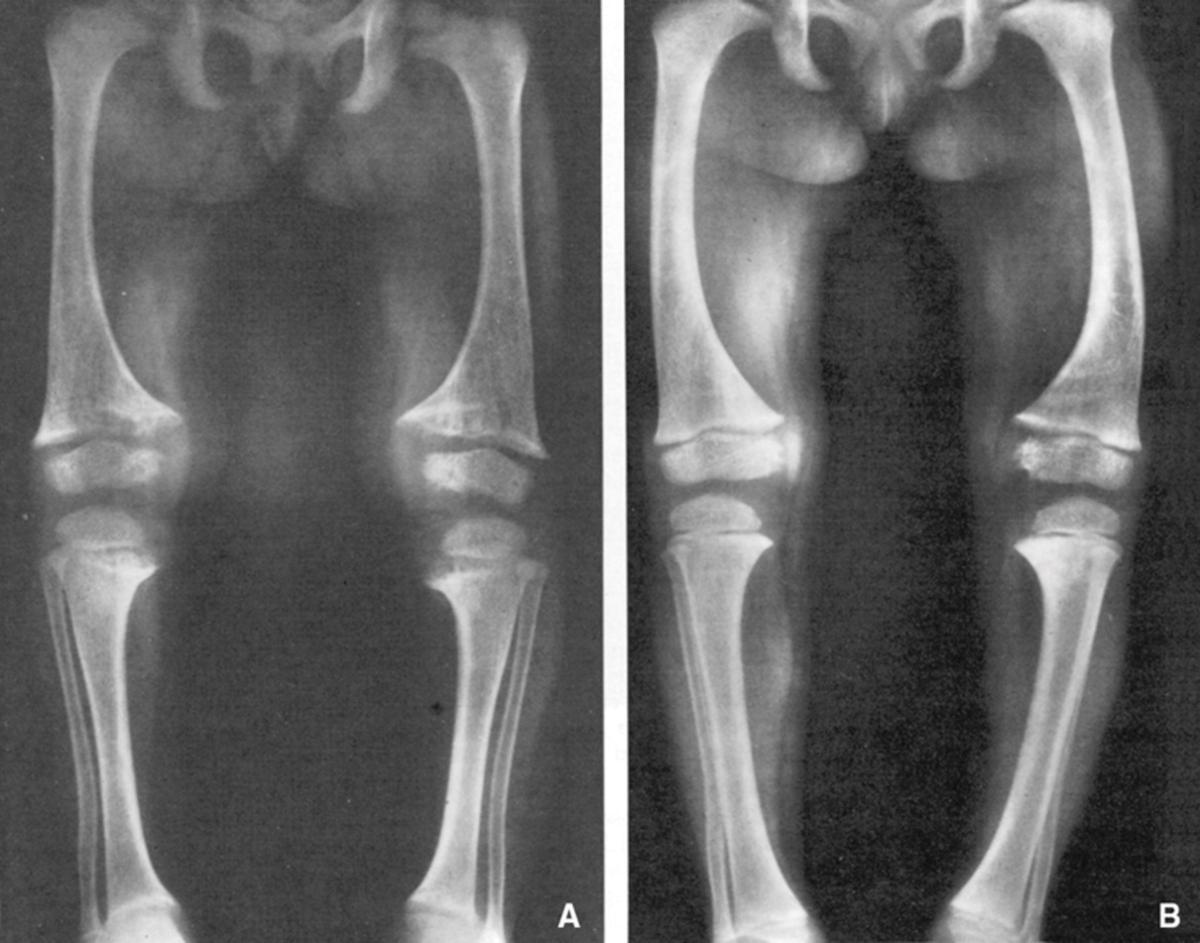

Se manifiesta durante las primeras edades con manifestaciones clínicas típicas del raquitismo como talla baja, dolor óseo y deformidades esqueléticas, especialmente, incurvación de las piernas.

Los pacientes también sufren “deformidades en extremidades inferiores, alteraciones dentales, pérdida auditiva, artrosis asociada a las deformidades esqueléticas y el desarrollo de fracturas, entre otras”, indica la doctora.

Si el tratamiento es óptimo, el pronóstico es bueno. Las deformidades esqueléticas, tan características de esta enfermedad, pueden corregirse mediante tratamiento médico y, si procede, cirugía ortopédica correctiva.